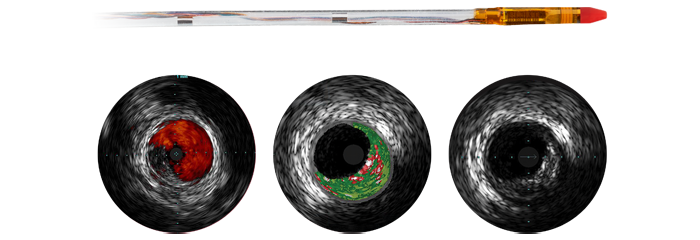

As more CAD patients are considered for minimally invasive interventional therapy, optimal treatment planning is hindered by the fact that 2D coronary angiography has limitations for detecting and assessing coronary stenosis. Data is not consistently and meaningfully connected pre- and intra-procedure, which adds time and complexity to treatment planning. We’ve designed our cardiology solutions to overcome these challenges so you can realise the benefits of clinical efficiency in the cath lab:

Image-guided therapy, iFR, IVUS and haemodynamic monitoring, as well as cardiac pre-procedure planning and advanced applications, are all connected to the image-guided therapy interface to allow viewing, manipulation and custom configuration on the monitor from a single controller at table side or from the control room.